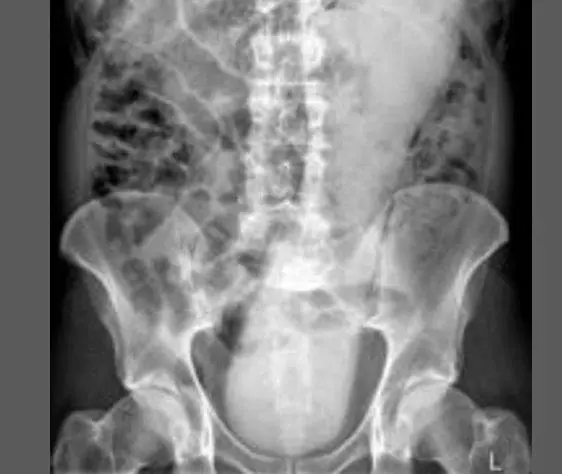

Oggetti bizzarri che hanno trovato la loro strada all'interno del corpo umano, e documentati grazie alle pazze radiografie raccolte dal dottor Frank Gaillard. Quest’ultimo ha fondato Radiopaedia.org, un sito collaborativo che raccoglie casi radiologici e articoli medici a tema.